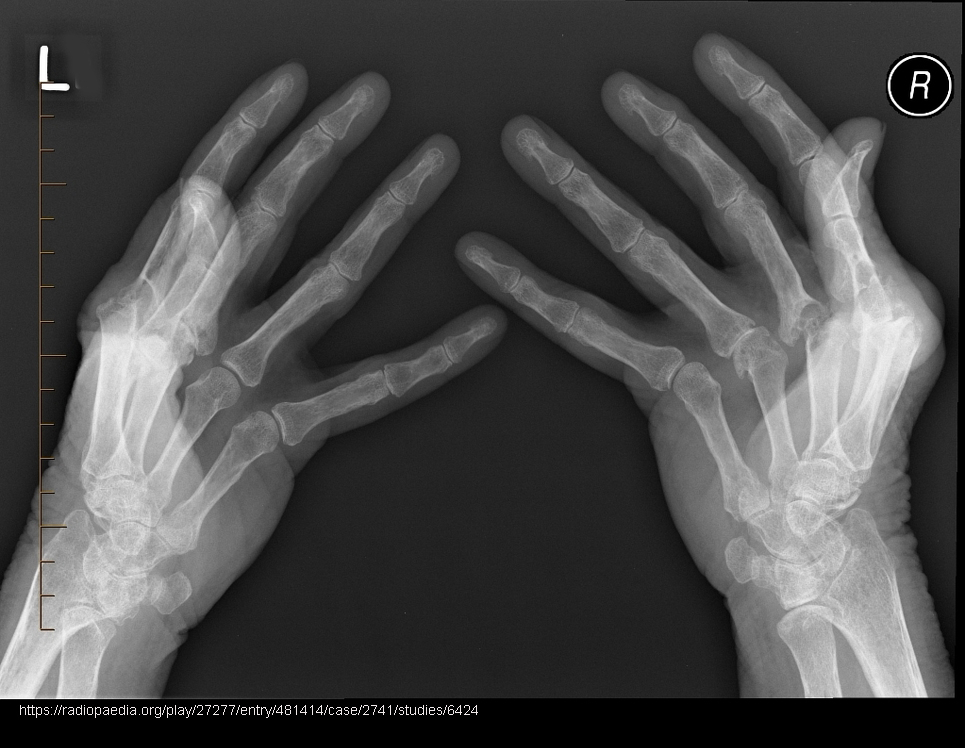

Radiographic signs of RA?

Early: minimal bony change; later: osteoporosis/rarefaction, deformities.